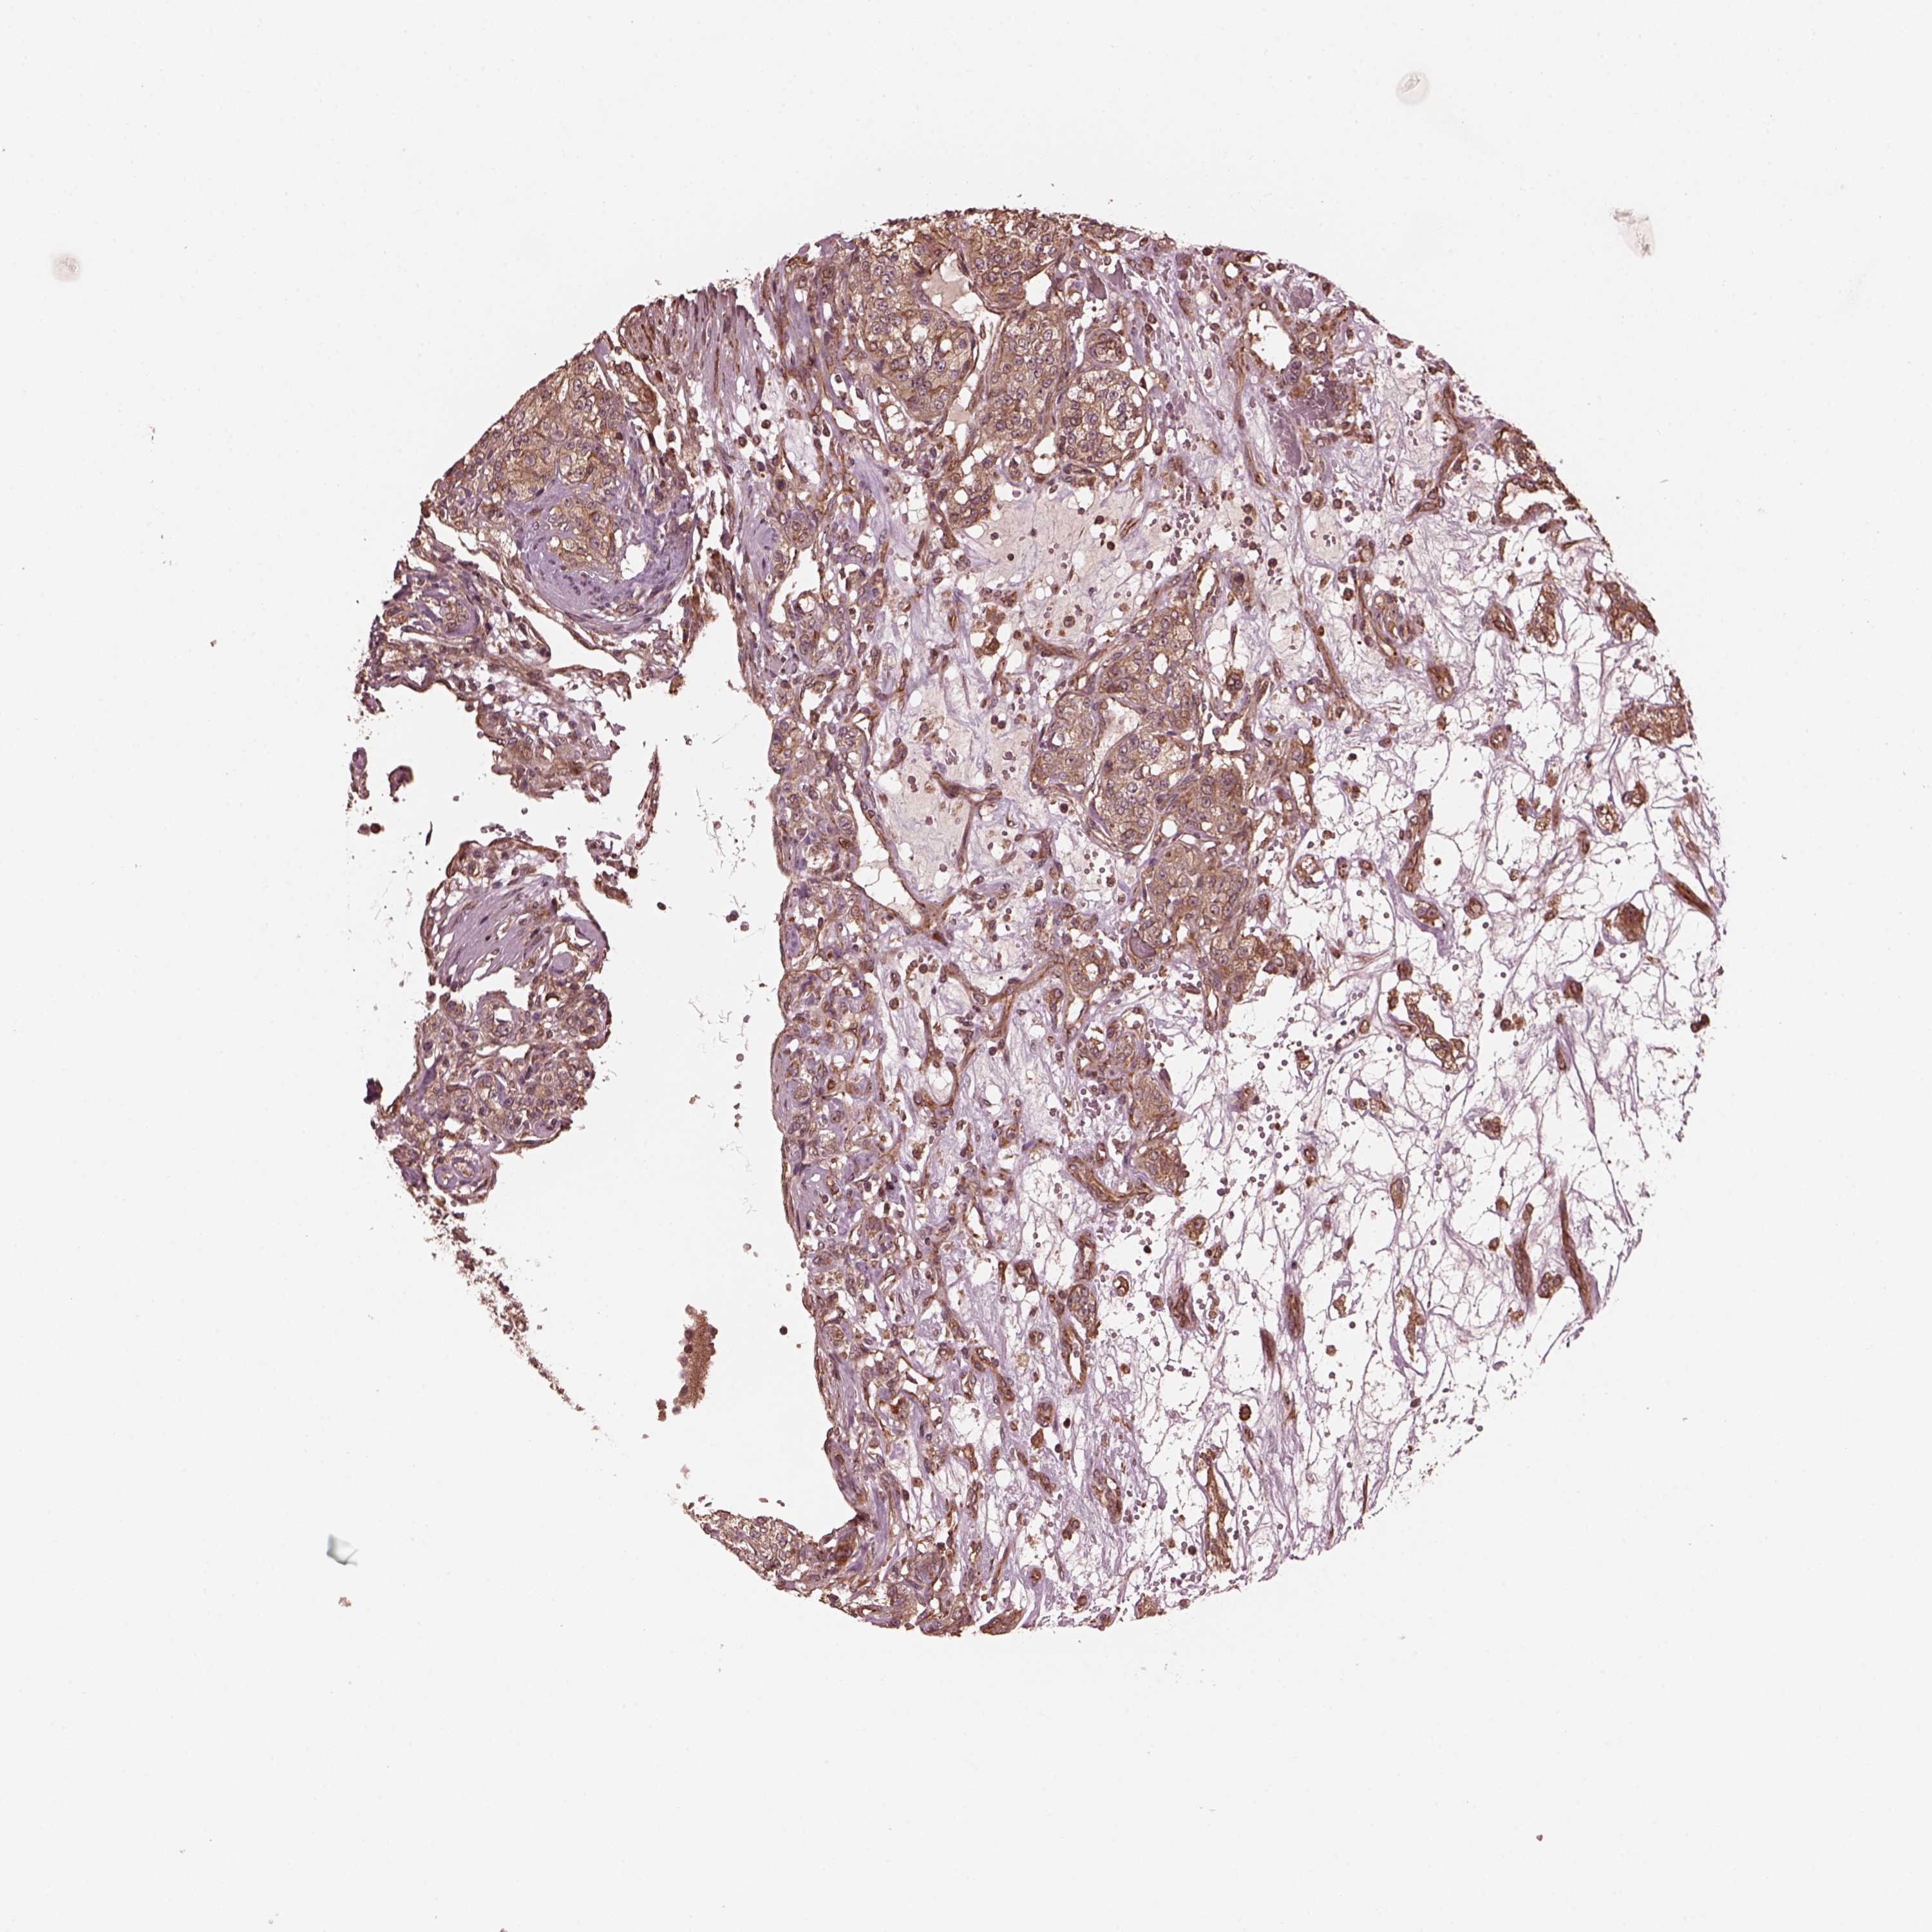

KIDNEY RENAL CLEAR CELL CARCINOMA (VALIDATION) - Interactive survival scatter ploti

The Survival Scatter plot shows the clinical status (i.e. dead or alive) for all individuals in the patient cohort, based on the same data that underlies the corresponding Kaplan-Meier plots. Patients that are alive at last time for follow-up are shown in blue and patients who have died during the study are shown in red.

The x-axis shows the expression levels (FPKM) of the investigated gene in the tumor tissue at the time of diagnosis. The y-axis shows the follow-up time after diagnosis (years). Both axes are complimented with kernel density curves demonstrating the data density over the axes. The top density plot shows the expression levels (FPKM) distribution among dead (red) and alive patients (blue). The right density plot shows the data density of the survived years of dead patients with high and low expression levels respectively, stratified using the cutoff indicated by the vertical dashed line through the Survival Scatter plot. This cutoff is automatically defined based on the FPKM cutoff that minimizes the p-score. The cutoff can be changed by dragging the vertical line or by entering a cutoff value in the square labeled "Current cut-off".

Under the Survival Scatter plot the p-score landscape (black curve; left axis) is shown together with dead median separation (red curve; right axis). Dead median separation is the difference in median mRNA expression between patients who have died with high and low expression, respectively. It is calculated as follows: median FPKM expression of dead patients with high expression - median FPKM expression of dead patients with low expression. This is intended to aid the user in visually exploring custom cutoffs and the associated p-scores and dead median separation.

Individual patient data is displayed and can be filtered by clicking on one or more of the category buttons on the top of the page. Categories describing expression level and patient information include: high, low, alive, dead, female, male and tumor stages. The scale of the x-axis can be toggled between linear and log-scale by clicking on the "x log" button. Mouse-over function shows TCGA ID, patient information and mRNA expression (FPKM) for each patient.

& Survival analysisi

Kaplan-Meier plots summarize results from analysis of correlation between mRNA expression level and patient survival. Patients were divided based on level of expression into one of the two groups "low" (under cut off) or "high" (over cut off). X-axis shows time for survival (years) and y-axis shows the probability of survival, where 1.0 corresponds to 100 percent.

ZNF292 is validated prognostic, high expression is favorable in Kidney Renal Clear Cell Carcinoma (validation)

Best expression cut offi

Based on the FPKM value of each gene, patients were classified into two groups and association between prognosis (survival) and gene expression (FPKM) was examined. The best expression cut-off refers the FPKM value that yields maximal difference with regard to survival between the two groups at the lowest log-rank P-value. Best expression cut-off was selected based on survival analysis .

When clicking on this number, the vertical dashed line indicating cut-off, the interactive survival plot, and the Kaplan-Meier curve will be adjusted to show results based on the best expression cut-off.

: 12.28

TCGA RNA samplesi

RNA-seq data is reported as average FPKM (number Fragments Per Kilobase of exon per Million reads), generated by the The Cancer Genome Atlas (TCGA) .

Normal distribution across the dataset is visualized with box plots, shown as median and 25th and 75th percentiles. Points are displayed as outliers if they are above or below 1.5 times the interquartile range. FPKM values of the individual samples are presented next to the box plot.

Average pTPM 14.4

Number of samples 100